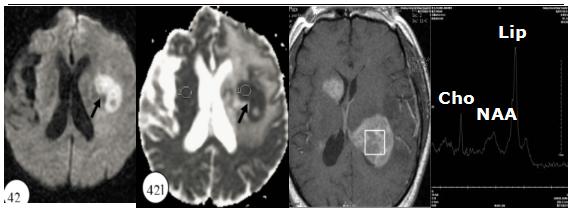

图 DWI与MRS

(1)三者相似点:cho峰增高,NAA峰降低,部分可见Lac与Lip。

(2)三者不同点:肿瘤的cho峰增高显著,多超过2倍的NAA峰; PCNSL可出现高大的Lip峰,少数胶母也可出现高大Lip峰,可能与坏死相关;β,γ-Glx峰升高对于TDL与肿瘤的具有一定特异性。